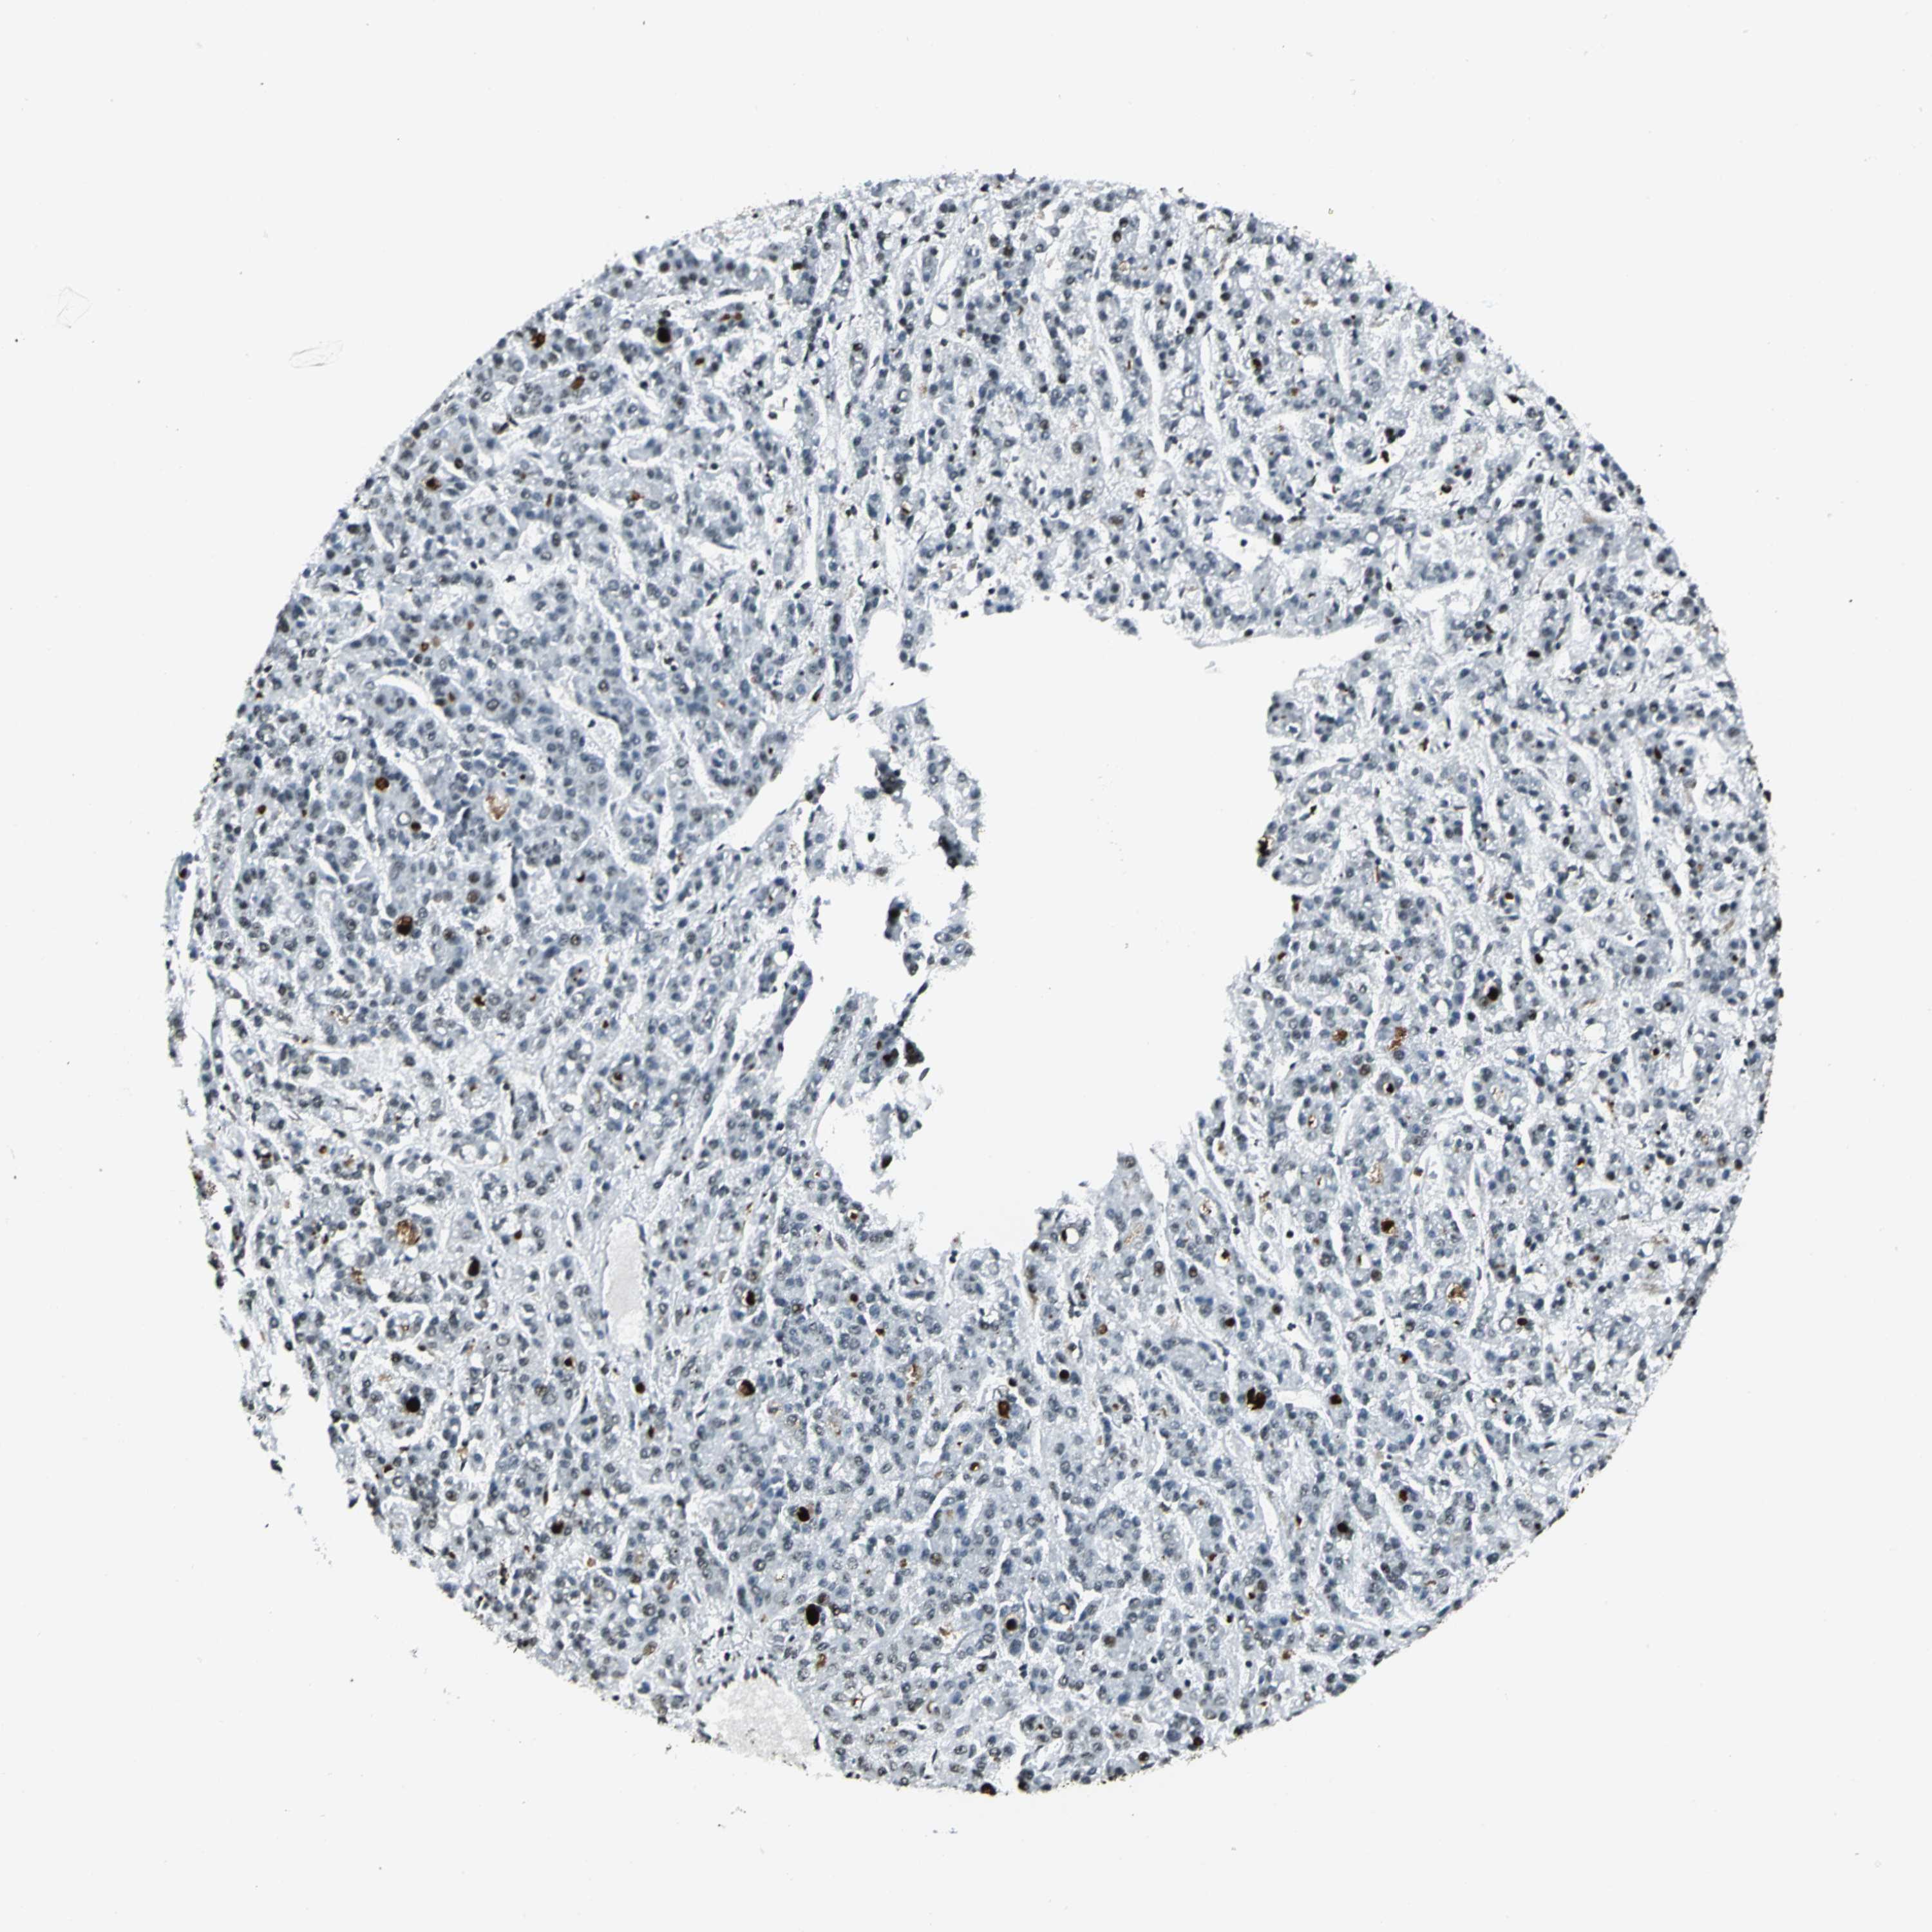

LIVER CANCER - Protein expressioni

A mouse-over function shows sample information and annotation data. Click on an image to view it in a full screen mode. Samples can be filtered based on level of antibody staining by selecting one or several of the following categories: high, medium, low and not detected. The assay and annotation is described here.

Note that samples used for immunohistochemistry by the Human Protein Atlas do not correspond to samples in the TCGA dataset.

Antibody stainingi

Antibody staining in the annotated cell types in the current human tissue is reported as not detected, low, medium, or high, based on conventional immunohistochemistry profiling in selected tissues. This score is based on the combination of the staining intensity and fraction of stained cells.

Each image is clickable and will lead to virtual microscopy that enables deeper exploration of all samples and also displays staining intensity scores, fraction scores and subcellular localization as well as patient and tissue information for each sample.

Antibody HPA004873

Antibody CAB004497

Staining

High

Medium

Low

Not detected

Intensity

Strong

Moderate

Weak

Negative

Quantity

>75%

75%-25%

<25%

None

Location

Nuclear

Cytoplasmic/membranous

Cytoplasmic/membranous,nuclear

Cholangiocarcinoma

Carcinoma, Hepatocellular, NOS